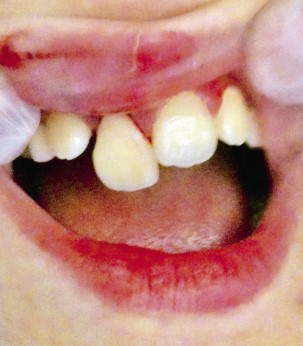

Entre los determinantes orales o factores predisponentes orales, destacan la existencia de unos dientes incisivos superiores protruidos, con un resalte u overjet de más de 3 mm (Fig. 1) como consecuencia de una maloclusión o el uso excesivo de chupete o hábito de succión de dedo, o la existencia de un labio corto o incompetente que no cubra en su totalidad a los dientes(5)(Tabla I).

Figura 1. Maloclusión con resalte-overjet

Los traumatismos dentales son más frecuentes: en casos de protrusión de los incisivos, por uso excesivo de chupete, hábito de succión de dedo, labio superior corto que no cubre a los dientes y la incompetencia labial.